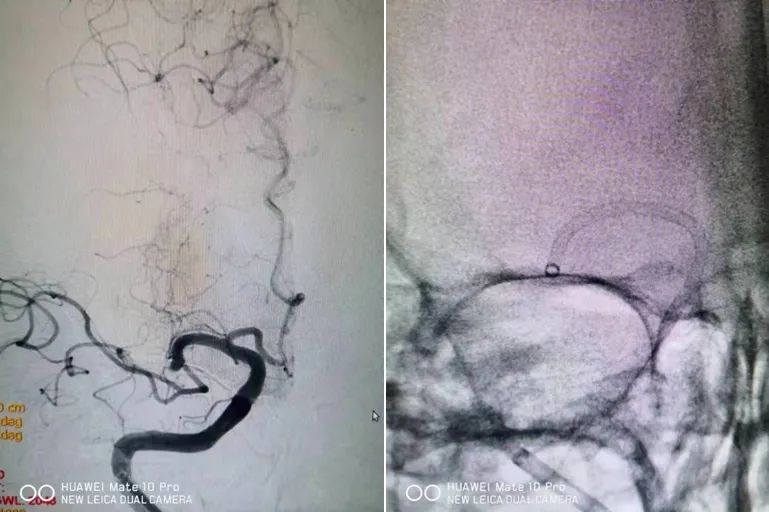

患者男性,84岁,因突发言语不清左侧肢体无力5小时由外院转入,入院时查体:嗜睡,双眼向右侧凝视,左侧肢体偏瘫肌力0级,NIHSS评分14分。外院CTA提示右侧大脑中动脉闭塞,CTP提示存在较大缺血半暗带。团队立即启动绿色通道绕行急诊直接送介入手术室,在局麻下行介入取栓治疗,造影证实右侧大脑中动脉M1段闭塞,使用大口径中间导管接触血栓抽吸出大量血栓,从穿刺到血管再通仅用了5分钟时间,患者在手术台上左侧肢体肌力即刻恢复。

脑血管造影提示右侧大脑中动脉M1段闭塞,使用抽吸导管抽吸开通血管

复查造影血管通畅,患者肢体力量即刻恢复

成功救治后,团队没有松懈,继续全面筛查患者病因,以制定相应二级预防方案防止卒中再次复发。因为患者活动中起病,症状迅速达到高峰,血栓清除术后造影证实头颈部血管未见明显狭窄闭塞,除外大动脉粥样硬化性及夹层等常见病因,综合临床影像资料考虑为心源性栓塞,经过心脏彩超未见密切结构性心脏病变,三次常规心电图及24小时动态心电图检查均未见房颤等心率失常,高度怀疑为阵发性房颤所致。